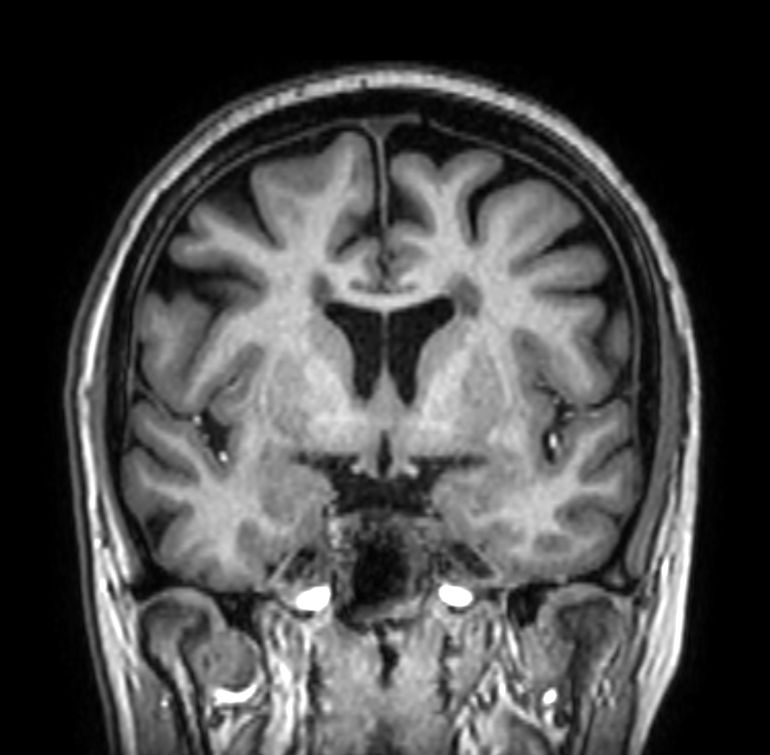

Multiple Sclerosis versus TIA

Standardized Multiple Slerosis MRI protocols typically require long scan times. Addition of Compressed SENSE enables faster exams, without compromise in image quality1. SWIp sequence has a high sensitivity to enhance contrast for deoxygenated (venous) blood or calcium deposits. This may help, when used in combination with other clinical information, in the diagnosis of various neurological pathologies. 3D (BrainVIEW) lets you acquire high resolution data in multiple directions in one scan. Isotropic voxel size enables reformats in any plane without loss of resolution.

3D Double IR BrainVIEW (reformat) Compressed SENSE

3D Double IR BrainVIEW Compressed SENSE